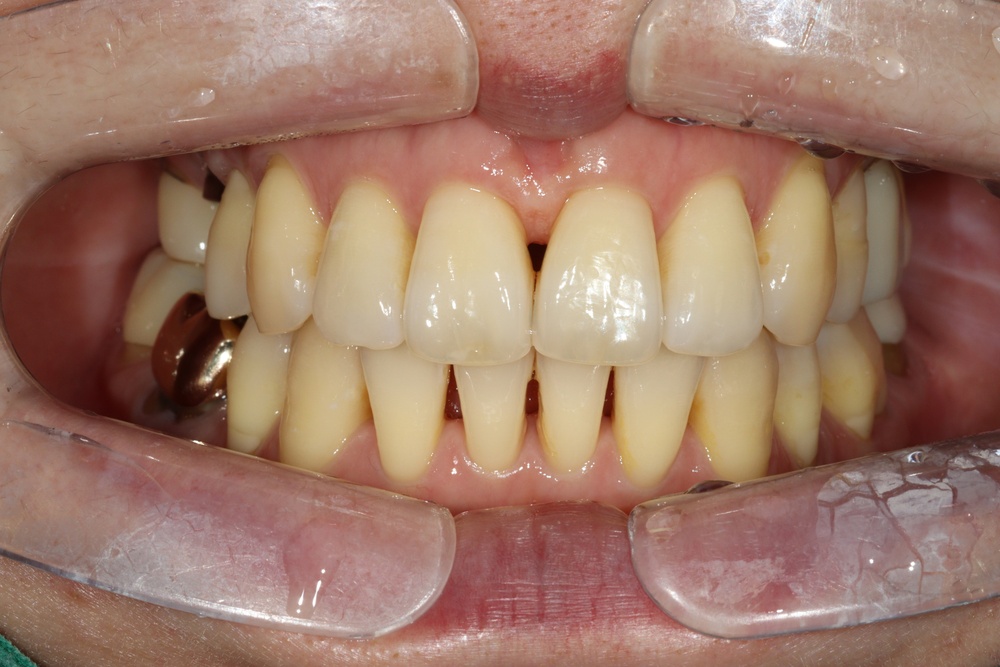

아래쪽 두 번째 어금니(제2대구치)가 선천적으로 없는 결손치로서, 사랑니(제3대구치)가 있으나 앞으로 쓰러져서 잘 안 씹히고 썩어 있습니다.

이런 경우 사랑니를 발치하고 임플란트를 하는 방법도 있으나, 본인 치아를 살리고 싶어하셔서 교정으로 접근하였습니다.

(본원은 교정과 임플란트 모두 다루므로 각 방법의 장단점을 충분히 비교 설명드렸습니다)

부분교정을 통해 누워있던 사랑니를 세웠으나, 씹는 면에 충치가 있습니다.

교정종료 후 보철치료(인레이)를 통해 씹는 기능을 회복시켰습니다.

누워있던 이가 세워져서 음식물이 더 잘 씹히게 되었습니다.

또한 음식물이 끼지 않게 되어 구강위생관리도 원활하게 되었습니다.